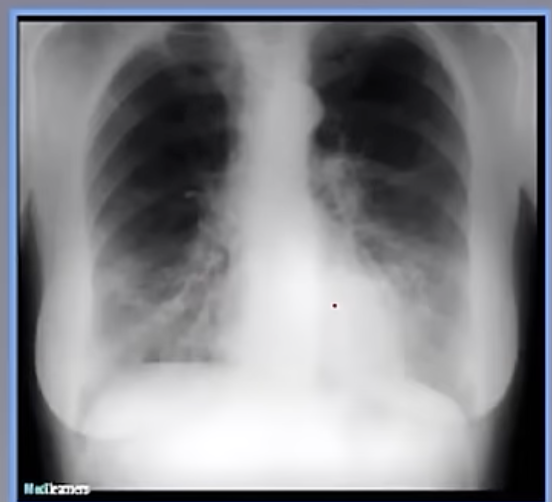

22

Q

Imagen de neumonia micronodular

A

la da Tb milliar o Histoplasmosis